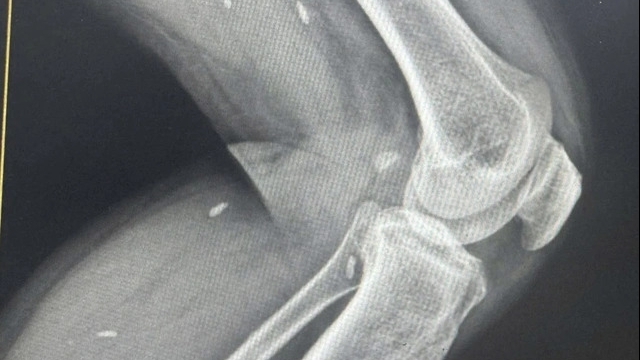

| Sau 14 ngày điều trị tích cực, bệnh nhân đã hồi phục tốt, chức năng tim cải thiện rõ rệt và đủ điều kiện xuất viện (Ảnh: BVCC) |

Sau 4 ngày điều trị, bệnh nhân được rút ECMO thành công. Sau 14 ngày điều trị tích cực, bệnh nhân đã hồi phục tốt, chức năng tim cải thiện rõ rệt và đủ điều kiện xuất viện.